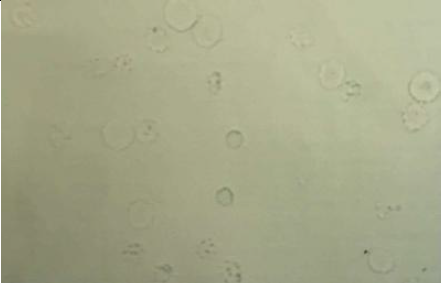

A. identify the slide

B. Is this only present in urine of sick people?

A. hyaline cast

B. no